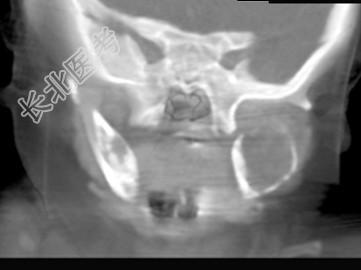

- 单项选择题男,2岁, 左侧颜面部、右肩部肿块,疼痛, 结合图像,最可能的诊断是 ( )

A、骨结核

B、骨髓炎

C、骨嗜酸性肉芽肿

D、骨囊肿

E、骨肉瘤